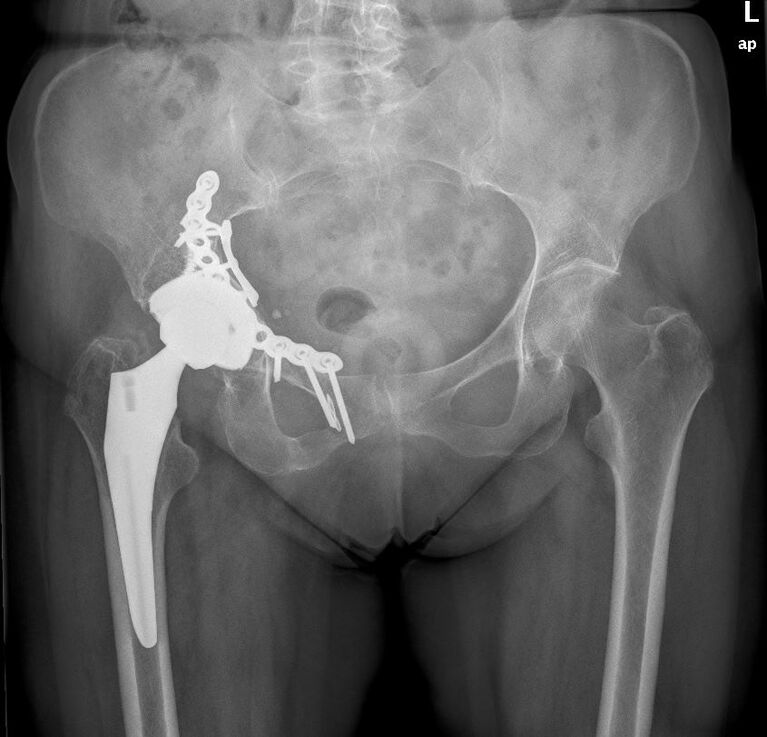

Bei schweren Unfällen kann es außerdem zu einem Hüftpfannenbruch (= Acetabulumfraktur) kommen. Primär steht zunächst die Rekonstruktion der Hüftpfanne im Vordergrund. Aufgrund des Risikos einer posttraumatischen Arthrose ist jedoch nicht selten frühzeitig (ggf. noch im Rahmen des ersten stationären Aufenthaltes) oder im Verlauf (zum Teil viele Jahre nach dem Unfall) die Implantation einer Hüfttotalendoprothese erforderlich.